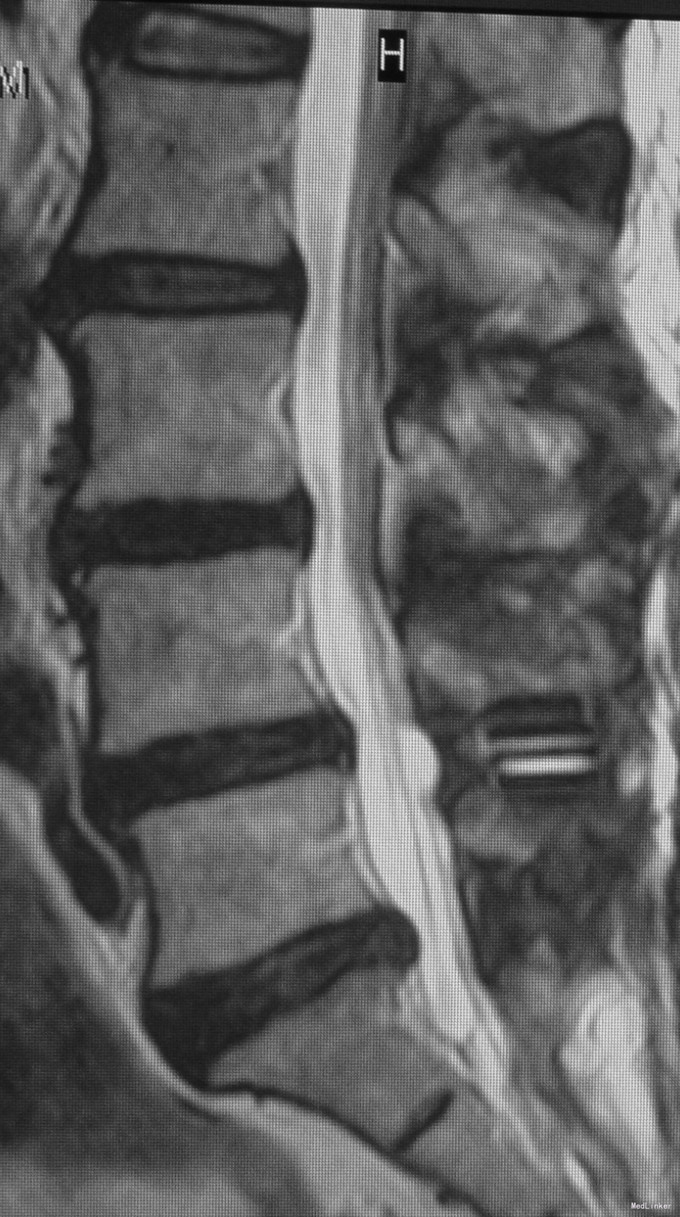

查体:脊柱生理弯曲存在,腰椎活动受限,L4/L5棘突压痛叩痛,叩击痛。双侧直腿抬高试验(-)。双下肢皮肤感觉正常,双侧髂腰肌、股四头肌、双侧胫前肌、踇背伸肌肌力Ⅳ级,腹壁反射、肛门反射正常,两侧膝正常,双侧踝反射未引出。双侧Babinski征(-),双侧皮温及色泽正常,双侧足背动脉搏动良好。 辅助检查:X光片示:动力位片显示腰椎4/5椎间失稳。MRI检查显示:腰4/5椎间盘突出,黄韧带肥厚致椎管狭窄,相应节段硬膜囊受压改变。

诊断:腰4/5椎管狭窄并失稳症。 治疗:给予行后路腰4/5右侧椎板间开窗减压椎间盘摘除并肥厚黄韧带切除+棘突间wallis固定术。

随访示患者腰痛及双下肢跛行症状明显缓解。 讨论:该例患者临床症状主要为腰痛并间歇性跛行,椎间盘突出合并黄韧带肥厚致椎管狭窄,且存在轻度失稳,故给予椎管减压并棘突间wallis动态固定。术后效果满意。